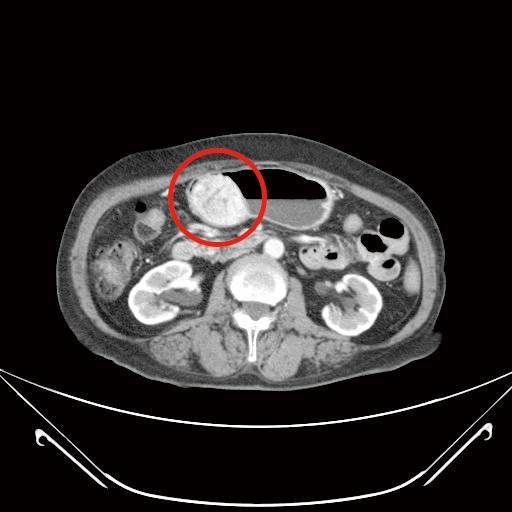

膽囊炎(上圖)

72歲林女士,3年前經上消化道內視鏡檢查發現有個2公分大的胃黏膜下腫瘤,疑似胃腸道基質瘤,持續門診追蹤,近期發現腫瘤緩慢長大,2個月前因上腹部悶痛且頭暈就診,由於合併有血便症狀,經上消化道內視鏡及電腦斷層檢查,發現腫瘤已接近6公分,且膽囊被結石塞滿,沒有膽汁的空間,經過和病人及家屬充分討論,醫療團隊以達文西系統機器手臂輔助腹腔鏡手術,為病人進行部分胃切除以及膽囊切除手術,手術順利,病人於術後第9天出院。病理化驗報告證實胃部腫瘤屬於低度分化惡性胃腸道基質瘤,評估後僅需定期追蹤檢查,膽囊則是慢性膽炎。